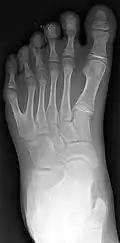

Right-sided duplication of the right little toe in an 8.5 months old male, with two toes (fifth and sixth) apparently forming joints with the fifth metatarsal bone, which is mildly broadened distally. The duplicated toes have almost normal growth. The fifth toe has mild varus angulation, and the sixth toe has substantial valgus angulation.

X-ray of type III central polydactyly (the middle fingers are the same length).

Classification is performed by using x-ray imaging to see the bone structures.[19]